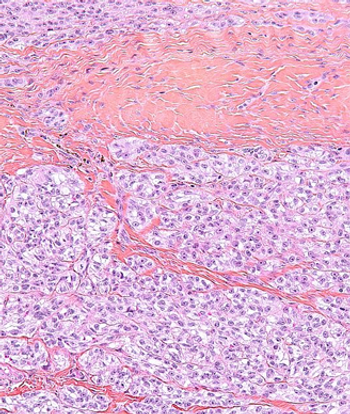

This slide show features a CT image, and pathology images of gastrointestinal stromal tumors (GISTs) arising in the stomach using H&E, CD34, and c-Kit staining.